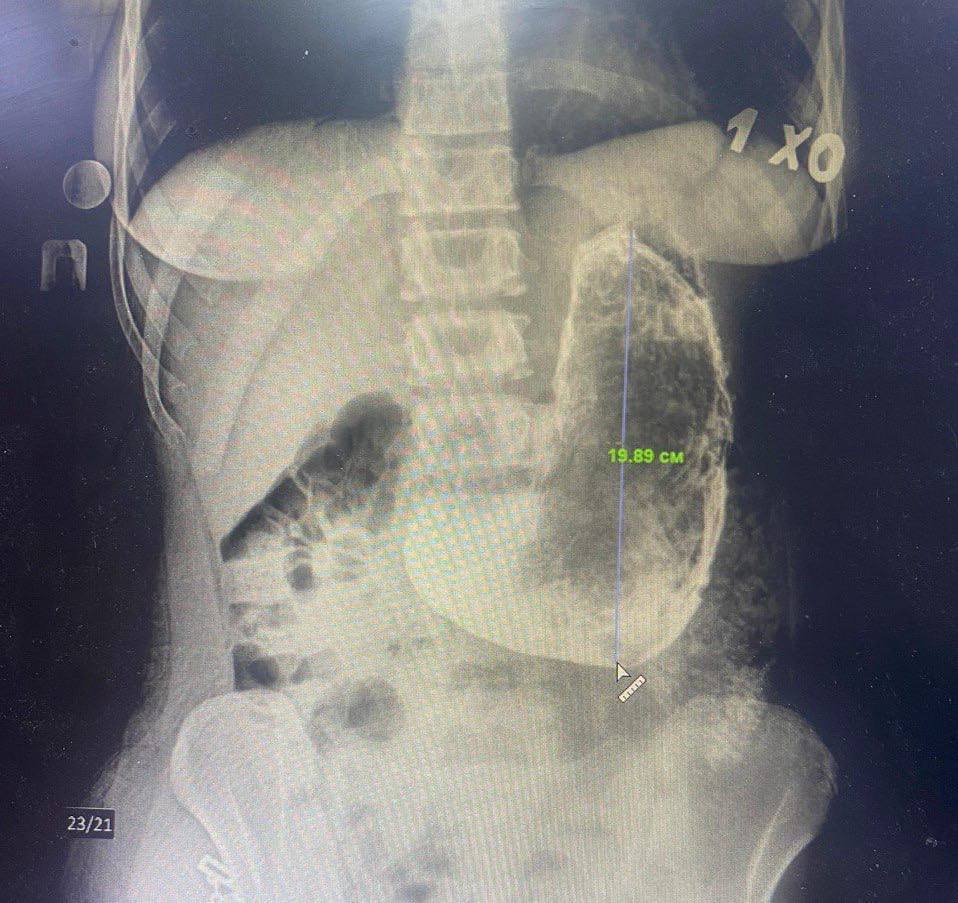

Cuando esos síntomas se hicieron ya insoportables, solicitó ayuda médica, explicando que estuvo tomando las píldoras a lo largo de los dos últimos meses. La exploración reveló que la paciente tenía en su estómago un cuerpo extraño de unos 20 por 15 centímetros.

Debido al tamaño y la densidad del bezoar —acumulación de alguna sustancia no digerible—, los médicos decidieron operar a la mujer y extraer esa formación a través de una pequeña incisión. Uno de los especialistas dijo que solo será posible hablar con precisión sobre la composición del bezoar y las razones de su aparición cuando los resultados del examen histológico estén listos.